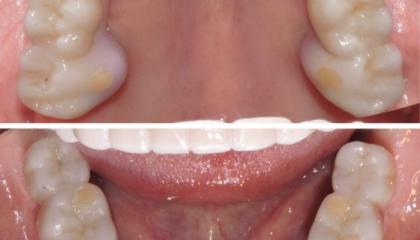

After